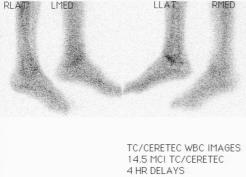

Nuclear Scan Images of Lower Torso & Lower Legs

These images were captured in order to determine why Liam’s bones broke so easily playing a video game and to also determine if there

was any Osteomyelitis. This is the diagnosis report from the scan. "There is mild increased activity noted in the lateral side of the left

ankle. However the patient does have a cast on the left leg. This uptake can be secondary to either inflammatory or infectious change within

either the skin or adjacent bone." Various contrast were used to enhance image details. The last images reminds one of the Shroud of Turin.

Hummm, makes one wonder... ;-)